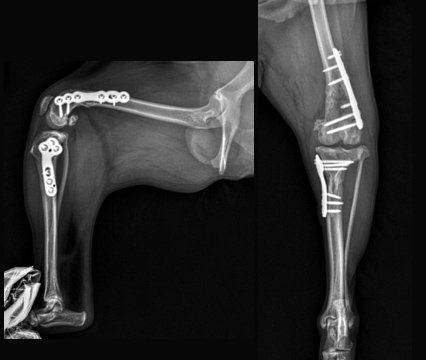

십자인대 질환

- TPLO

- 9살, 11kg, 아메리칸코커스패니엘

십자인대 질환에 대해 TPLO 수술을 진행하였습니다. 수술 직후 방사선에서 절골선이 보이지 않습니다.

정교하고 안정적인 수술로 다음날부터 산책이 가능합니다.

십자인대 질환

- 5 hole TPLO

- 11살 3kg 말티즈

다양한 회사의 플레이트 제품을 가지고 있어서 환자 맞춤으로 수술이 가능합니다.

일반적으로 TPLO 수술 시 6홀 플레이트를 사용하는데

이 환자의 경우 뼈가 작아 5홀 플레이트를 사용하여 교정하였습니다.